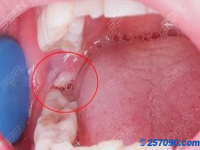

拔智齿真的可以瘦脸吗?拔智齿多少钱   拔智齿真的可以瘦脸吗?拔智齿多少钱。拔智齿后那个洞臭到恶心通常是因为食物残渣、干槽症、感染发炎等因素引起的,具体的原因需要到医院进行详细的检查,然后做针对性的治疗。  拔智齿那个洞会愈合吗  当一 2023-08-31 15:00:49